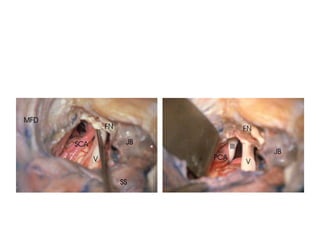

Infratemporal fossa approach type A

[ IFTA-A ] – transpetrous approach

There is no need to transpose facial

nerve in ITFA-A – Dr. Morwani

The structures that impede the lateral access to the lower skull

base, namely, the facial nerve (FN), the styloid process and

attached

muscles and ligaments, and the posterior belly of the digastric. ICA,

internal

carotid artery; IJV, internal jugular vein.

The mastoid segment of the facial nerve (FN) is centered

on

the jugular bulb (JB).